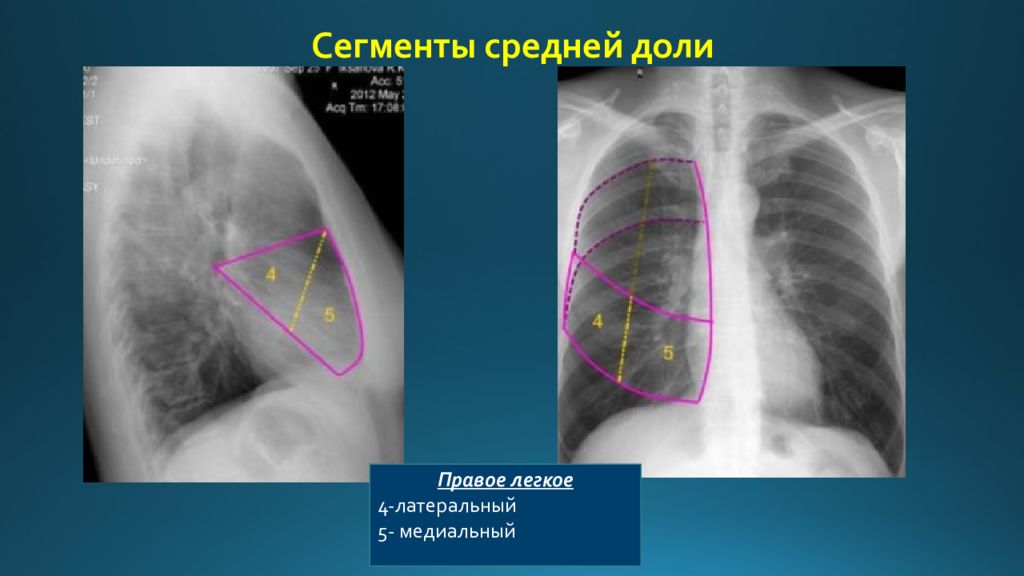

Анатомические изображения сегментов легких различных животных

Раздел: Другие животные